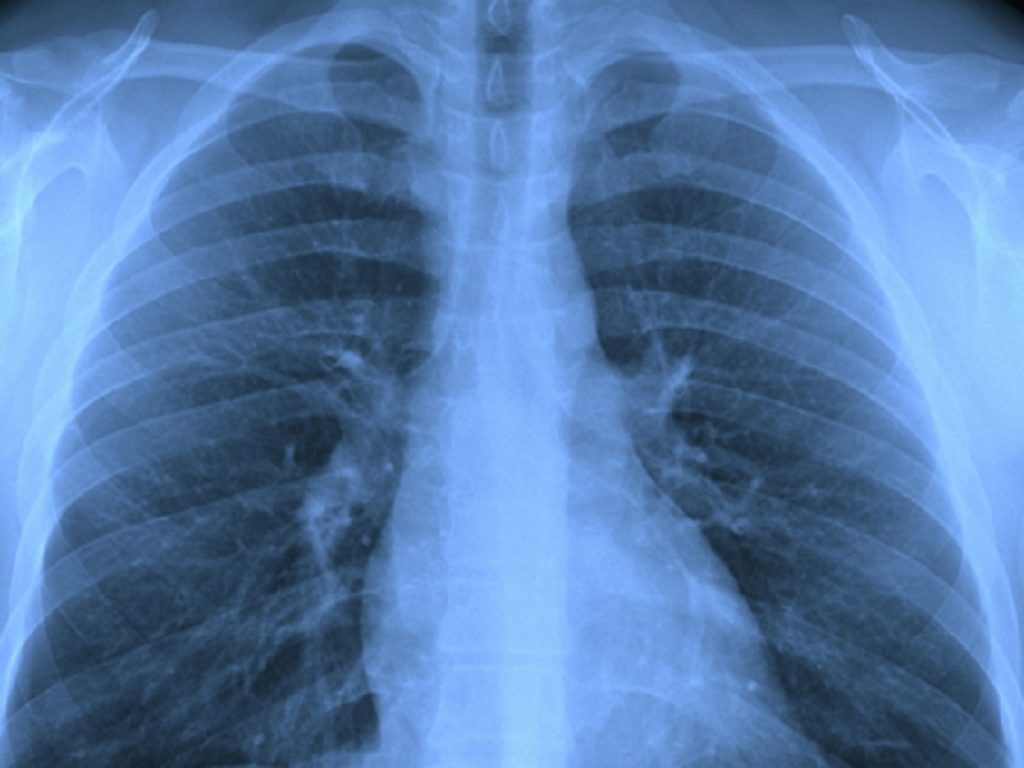

Cancro del polmone, nuovi dati su ifinatamab deruxtecan nell’ES-SCLC pretrattato: attività promettente e profilo di sicurezza gestibile

Ifinatamab deruxtecan (I-DXd) è un nuovo anticorpo-coniugato (ADC) ancora in fase sperimentale. I. Nello studio di fase 2 IDeate-Lung01 la dose di 12 mg/kg q3w ha mostrato una rilevante attività antitumorale in pazienti con carcinoma polmonare a piccole cellule in stadio esteso (ES-SCLC) già trattati. Lo studio è stato presentato durante la Conferenza mondiale sul cancro al polmone 2025 dell’Associazione internazionale per lo studio del cancro al polmone (IASLC).